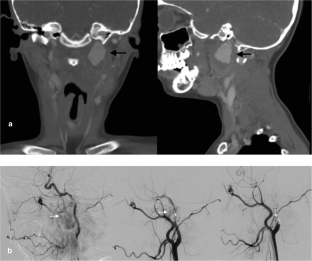

Fig. 1

Fig. 2

Fig. 3